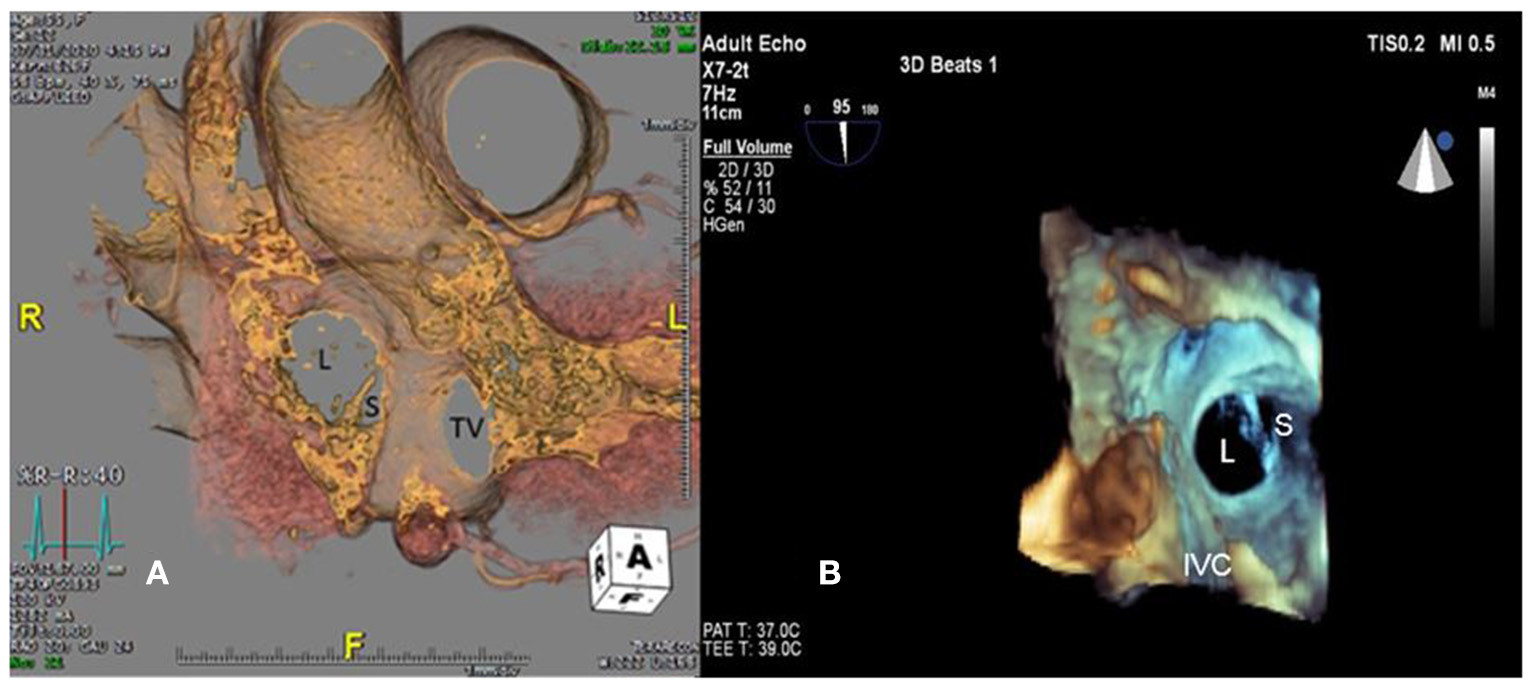

A 55-year-old female patient came to our hospital with a complaint of chest discomfort for 2 days. The electrocardiogram (ECG) revealed an incomplete right bundle branch (iRBBB) without ST segment elevation. Troponin-I, creatine kinase (CK), and creatine kinase-MB (CK-MB) levels were in the normal range. Chest X-ray revealed right ventricle hypertrophy (RVH) with prominent pulmonary congestion. Two secundum type ASDs with membranous remnants at the right atrium were noted in TTE. TEE was arranged for the membranous remnants at the right atrium and revealed double ASDs with iCTD at the connection of the right atrium and inferior vena cava (Figures 1A,B). Cardiac CT showed double ASDs, which were 21.2 and 13.6 mm in size, with iCTD (Figures 2A,B). During catheterization, no pulmonary hypertension was found, and the size of the larger ASD under balloon sizing was 29.2 mm. The ratio of pulmonary flow to systemic flow was 1.9:1. Therefore, a 30-mm Lifetech device was chosen to close these two ASDs. We chose a 7 French sheath to pass the larger ASD from the RA to LA and deploy the device to close the ASDs without detachment. However, transient heart ischemia with presence of ST segment elevation (Figure 3A) was noted and coronary sinus obstruction by the device was thought to be the cause. The shape of the device was also not feasible and many residual shunts were noted. Partial involvement of iCTD in the process of device deployment, which resulted in the obstruction of coronary sinus, was determined (Figure 4A). Hence, we withdrew the device immediately and the ST segment elevation recovered (Figure 3B).

Figure 2

Large (L) and small (S) ASDs are revealed in (A) cardiac computed tomography and (B) three-dimensional transesophageal echocardiogram. TV, tricuspid valve.